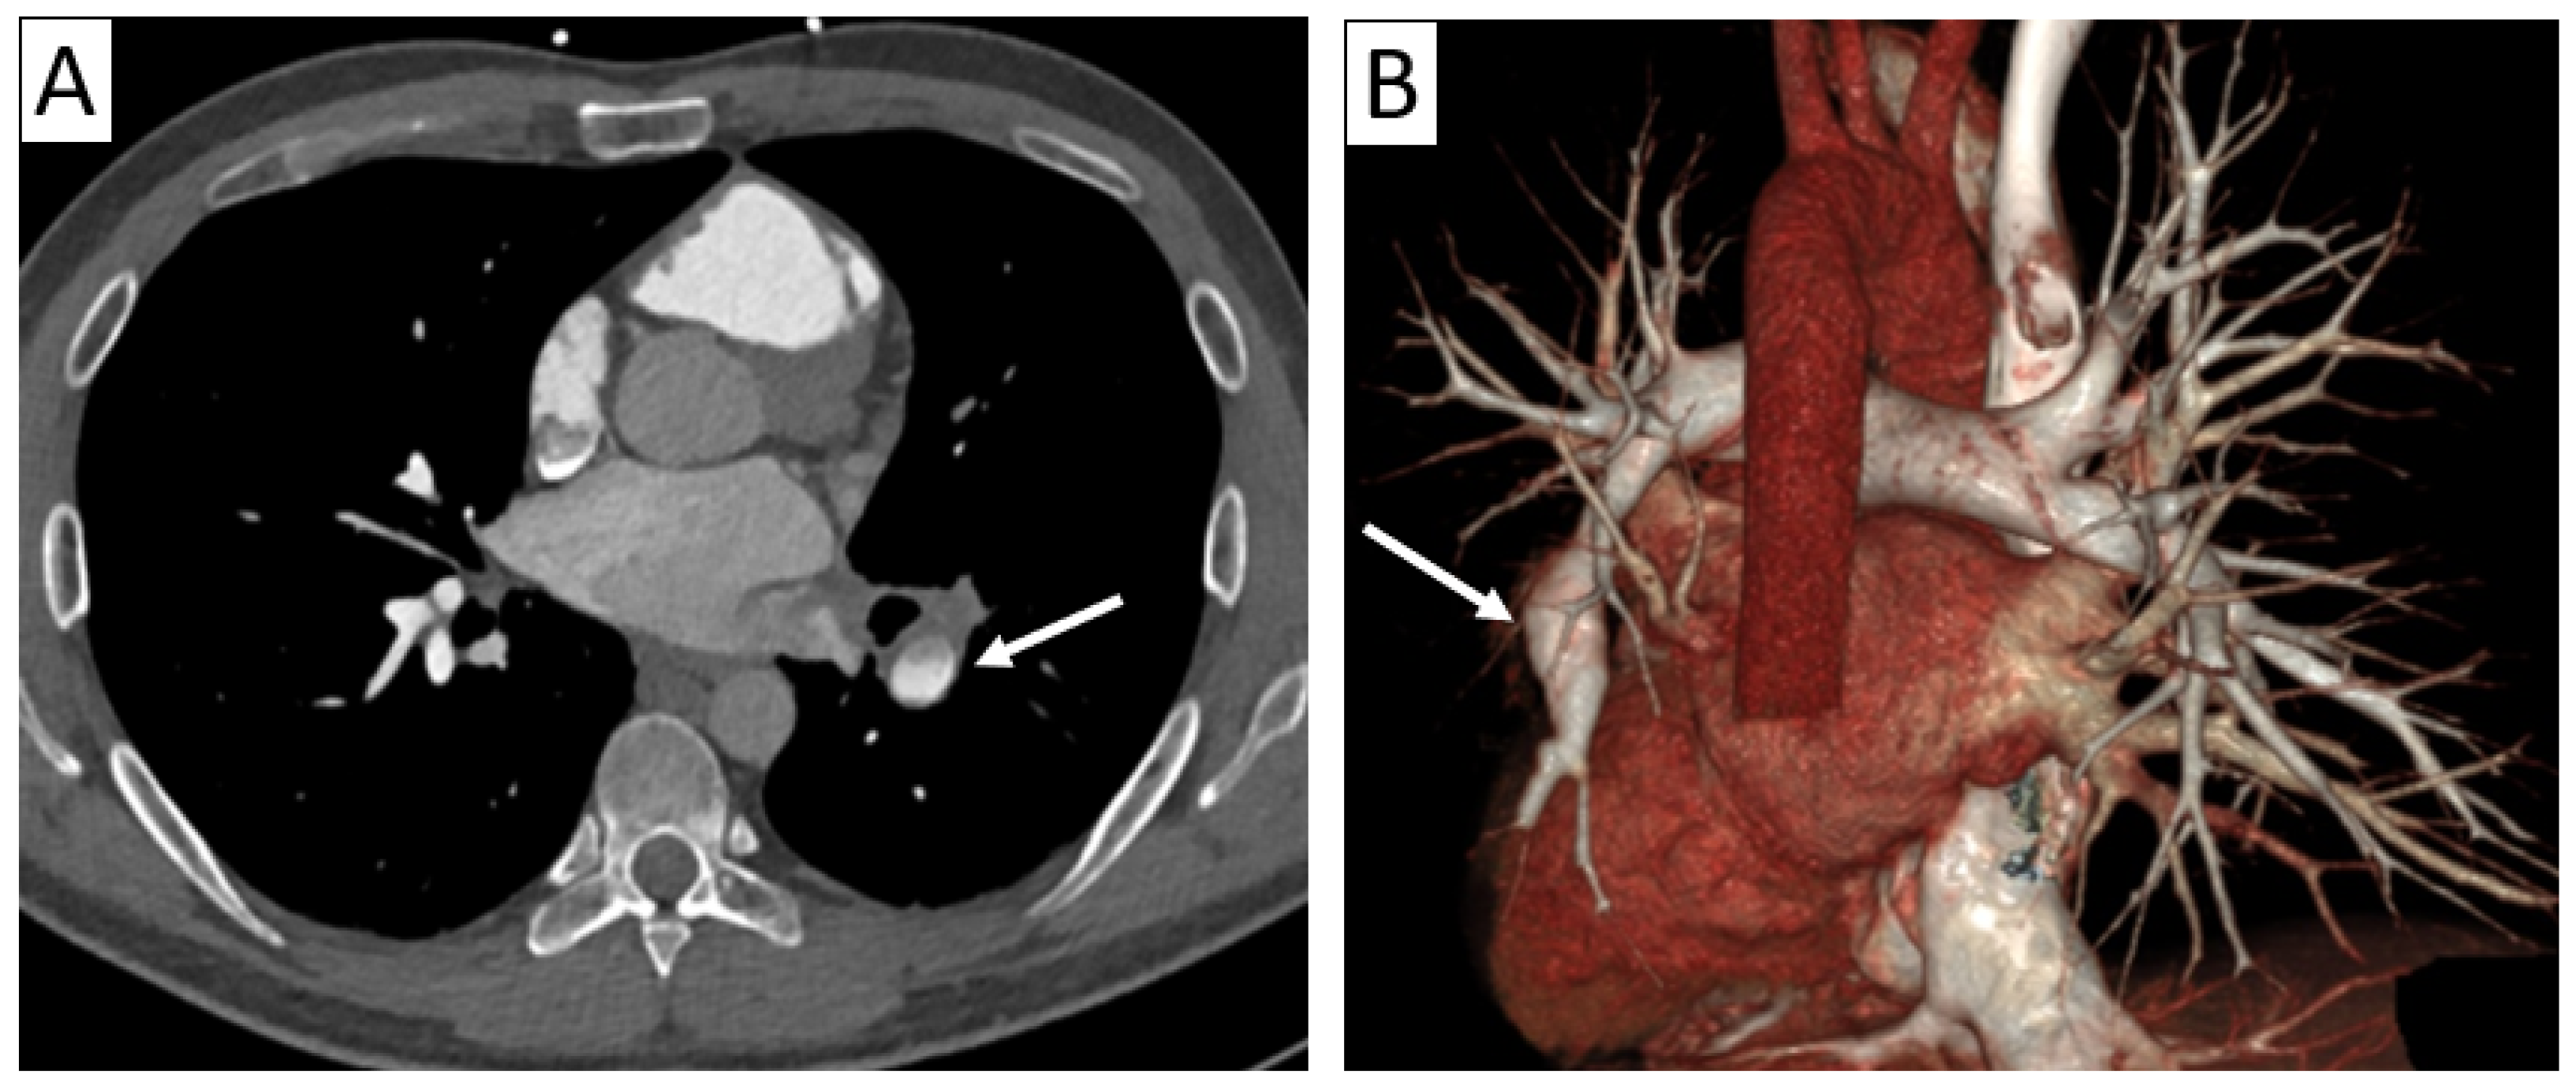

| CTA | Circumferential parietal thickening Vessel wall enhancement | Circumferential parietal thickening Vessel wall enhancement Luminal stenosis or narrowing |